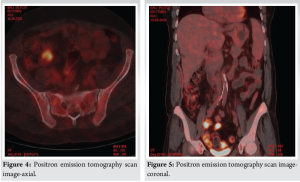

A 72-year-old female with a history of long-standing diabetes presented with fatigue, fever, and rashes on the upper limbs for 1 week. She denied any history of weight loss or loss of appetite. On physical examination, she exhibited no signs of distress, cyanosis, clubbing, raised jugular venous pressure, pedal edema, or lymphadenopathy. Her chest wall and spine were non-tender on palpation, and examinations of the abdominal, cardiovascular, pulmonary, and neurological systems were unremarkable. Laboratory investigations showed anemia (Hemoglobin: 6.4 g/dL) and severe thrombocytopenia (platelet count: 6000/μL) with a leukoerythroblastic blood picture on peripheral smear. Computed tomography (CT) scans of the abdomen and chest were unrevealing. Bone marrow aspiration and biopsy showed marrow spaces completely replaced by proliferating thin-walled vessels. In certain areas, clusters of plump spindle cells, likely endothelial cells, were observed. Immunohistochemical staining demonstrated that both the vessels and the spindle cells were strongly positive for CD31 and CD34, all suggestive of vascular neoplasia (Fig. 1). However, further positron emission tomography (PET) scan investigation revealed multiple non-avid lytic areas involving almost the entire visualized skeleton, suggestive of skeletal angiomatosis, and non-avid cystic lesions in the liver indicative of visceral angiomatosis, leading to the diagnosis of systemic cystic angiomatosis (Fig. 2-5).

The diagnostic findings that led to the differentiation of systemic cystic angiomatosis from vascular neoplasia included multiple non-avid lytic skeletal areas and non-avid cystic liver lesions on PET scan. The treatment with danazol and eltrombopag, although unconventional, was chosen based on the patient’s preference for conservative management.